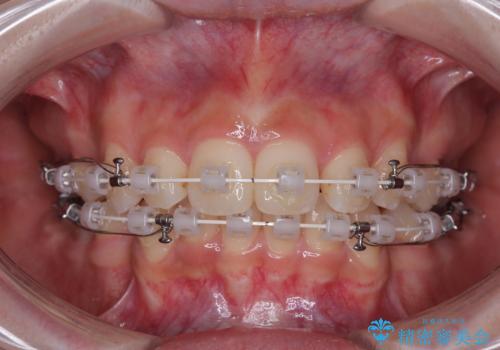

- 矯正装置

- 審美装置

- 上顎前歯の突出感を気にして来院された患者様です。

上下左右第一小臼歯4本を抜歯して、積極的に口元を引っ込めるよう、ワイヤー装置にて矯正治療を行うこととしました。